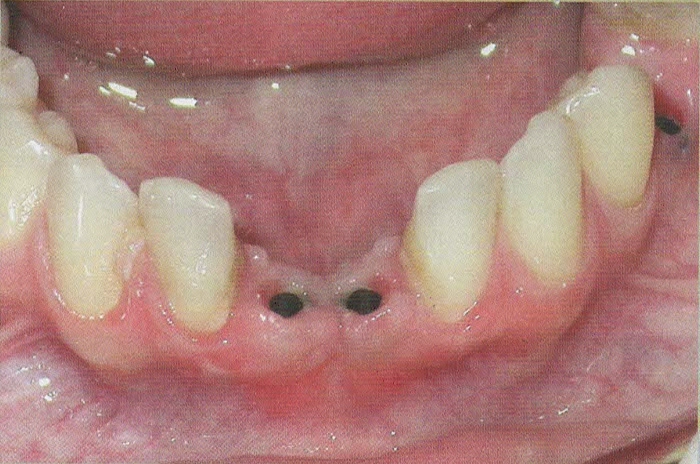

Per l'esecuzione delle impronte vengono usati materiali di prima qualità perchè la precisione delle impronte facilita la costruzione del manufatto e questo è un passaggio fondamentale per la buona riuscita della protesi.